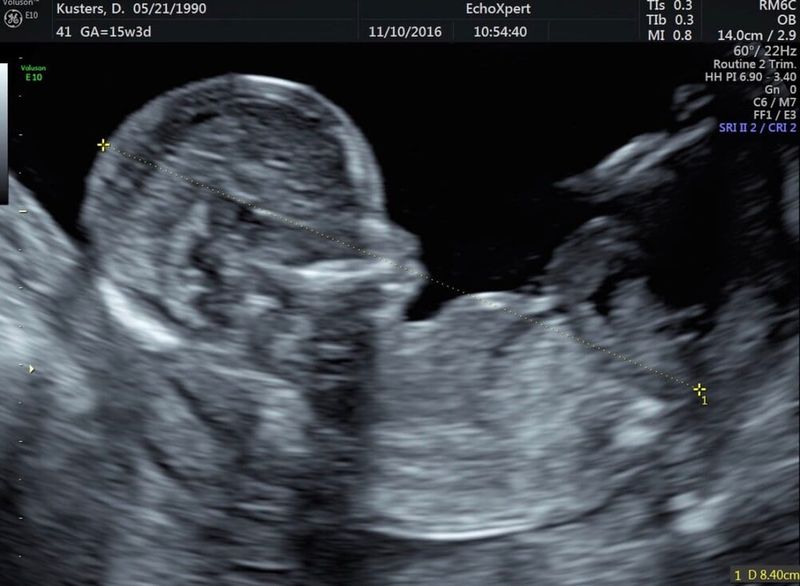

Jeje, finalmente el segundo trimestre y la ecografía de la fecha prevista. ¡Guau, este fue uno de los momentos más hermosos de mi vida! Un hermoso bebé saltando en mi vientre y ya tan completo. ¡Le agradecí a la ecografista con lágrimas en los ojos como 10 veces, a lo que ella respondió: 'Esto realmente lo han hecho ustedes mismos'. Alivio. Había sobrevivido la zona de peligro y mi embarazo ya no era un secreto. Las náuseas también podrían empezar a disminuir a partir de ahora, ¡aleluya! Pero a pesar de eso, no me sentía bien. Tenía poca energía y ganas para el día. 'Supongo que será por el dolor de pelvis y las náuseas, ¿verdad?'